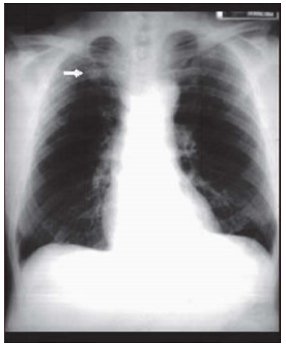

Homem com 35 anos de idade procura a Unidade Básica de Saúde devido a uma alteração identificada nos exames admissionais, reproduzida na radiografia de tórax seguinte. Refere tosse seca há 40 dias, constante, diária, nunca tratada. Nega febre, dispneia, hemoptise e perda de peso. É fumante, com uma carga tabágica de 20 anos.maço. O exame físico é normal. A conduta mais apropriada para este paciente, neste momento, é:

enunciado 1093890-1